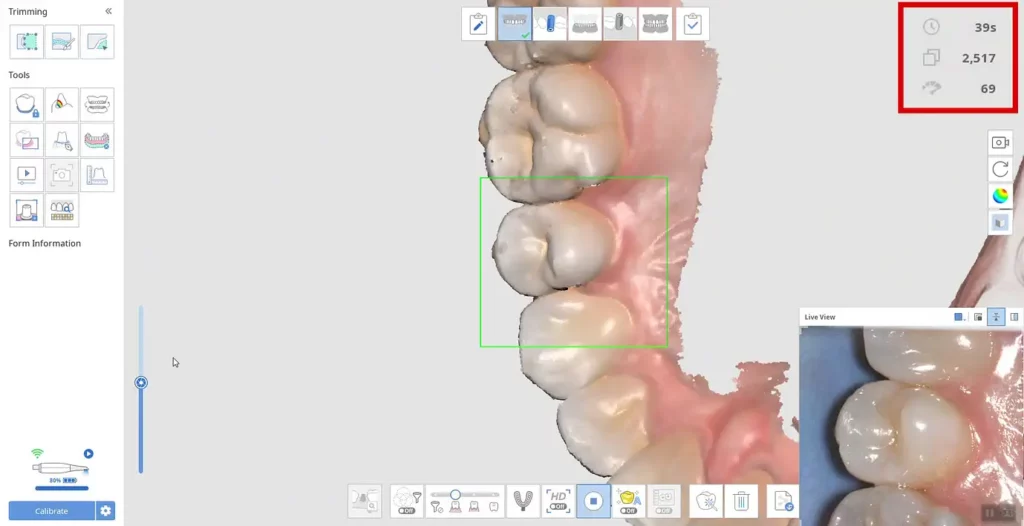

Scannerul Medit i600 reprezintă una dintre cele mai recente inovații în domeniu, combinând performanța înaltă cu accesibilitatea. Acesta oferă o acuratețe de 10.9 μm și o viteză de scanare de până la 35 FPS, fiind capabil să gestioneze diverse tipuri de scanări, inclusiv arcadă completă, segmente și implanturi. Designul ergonomic și greutatea redusă de doar 245 de grame îl fac ușor de utilizat, reducând oboseala utilizatorului și îmbunătățind confortul pacientului.

Scannerul Medit i600 este limitat la 35 FPS, ceea ce este suficient pentru a asigura o scanare fluidă și precisă în majoritatea situațiilor clinice.

Pentru cei care nu sunt familiarizați, FPS sau cadre pe secundă reprezintă frecvența imaginilor capturate de scanner. De exemplu, în informatică, la 30 FPS, 30 de imagini distincte apar succesiv într-o secundă. Dacă FPS-ul este prea scăzut, mișcarea va părea sacadată și neuniformă.

Medit i600 facilitează foarte bine fluxul de lucru al scanării pentru începători și utilizatorii experimentați. Ușurința de utilizare provine din software-ul care susține hardware-ul.

Partea care face ca scanerele Medit să strălucească este caracteristicile cuprinzătoare ale software-ului. Oferă o gamă impresionantă de diverse instrumente în timpul scanării și după – mai multe detalii în secțiunea de mai jos.